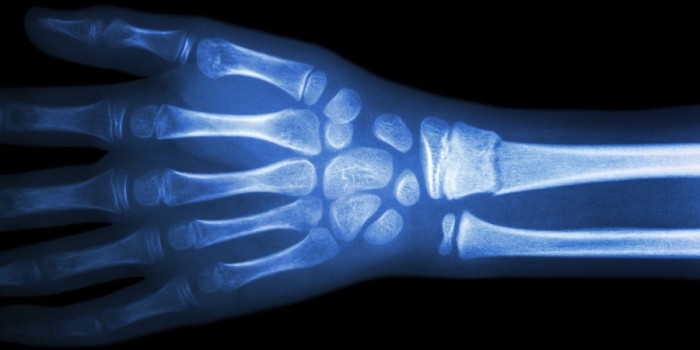

Dossier

In het artikel Toegang tot röntgendiagnostiek op de huisartsenpost (H&W 6, 2018)1 beschrijft Rutten de voordelen van toegang tot röntgendiagnostiek op de huisartsenpost (HAP). HAP’s die toegang hadden tot röntgendiagnostiek, verwezen 40% van de patiënten met een mogelijke fractuur naar de SEH; voor HAP’s zonder die toegang was dat 100%. Prachtige resultaten. Maar wat doe je als radiologie of een radioloog niet op elk uur van de dag beschikbaar is? In Zeeuws-Vlaanderen beoordeelt de dienstdoende huisarts zelf de foto’s.

Zeeuws-Vlaanderen is een dunbevolkte regio, met een huisartsenpost (HAP) bij het ziekenhuis in Terneuzen. De spoedeisende hulp (SEH) aldaar ontvangt alleen patiënten op verwijzing, dus praktisch alle spoedgevallen komen op de HAP terecht. Specialisten zijn in ANW-uren niet altijd aanwezig, de radioloog ook niet. In het eerste jaar van de huisartsenpost kozen de artsen er daarom vaak voor het röntgenonderzoek uit te stellen tot kantoortijd. Dat jaar kwamen er zo’n vijftig klachten over gemiste fracturen. Er waren creatieve oplossingen nodig om dit aantal terug te dringen. In 2003 besloten de huisartsen en radiologen gezamenlijk tot een innovatie: de huisartsen gingen zelf röntgenfoto’s beoordelen. Er werd een röntgenprotocol opgesteld en een radioloog verzorgde een avond ‘breukenscholing’ voor de huisartsen om hun expertise te vergroten.

De werkwijze sindsdien is als volgt. De dienstdoende huisarts op de HAP verwijst patiënten met een klinisch duidelijke fractuur rechtstreeks naar de SEH; in ANW-uren kan de huisarts bij twijfel röntgenonderzoek van de extremiteiten aanvragen. De röntgenlaborant maakt dan de foto en stuurt deze naar de HAP, waar de huisarts de foto beoordeelt in het kader van het klinische beeld. De patiënt krijgt een brief met informatie over het voorlopige karakter van deze beoordeling en het advies de volgende dag contact op te nemen met de eigen huisarts voor een definitief verslag.

Sinds het protocol in 2003 werd ingevoerd, is het aantal klachten over gemiste fracturen flink gedaald. In januari 2018 is aan vijftig huisartsen in Zeeuws-Vlaanderen een digitale enquête gestuurd over hun ervaringen. Van de 33 respondenten (66%) maakten er 29 (88%) regelmatig gebruik van de mogelijkheid om tijdens HAP-uren een röntgenfoto zelf te beoordelen. Te berekenen valt dat de huisartsen in de afgelopen 15 jaar een kleine 7000 röntgenfoto’s beoordeeld hebben, waarvan er 20 (0,28%) achteraf fout beoordeeld bleken. De radiologen bevestigen dat de fracturen die de dienstdoende arts over het hoofd zag bijna altijd kleine fissuren waren die geen consequenties hadden voor de behandeling op dat moment. Het lijkt er dus op dat huisartsen veilig zelf röntgenfoto’s van extremiteiten kunnen beoordelen. Van de 33 respondenten wilden er 22 (67%) doorgaan met deze werkwijze.